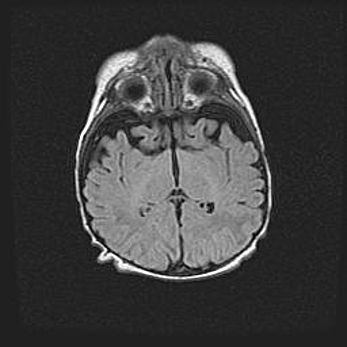

Лейкомаляция с кистозно-глиозной дегенерацией головного мозга.

Возраст: 2 месяца 25 дней

Вес: 6400 г

Окружность головы: 40 см

Срок гестации: 41 неделя

Лейкомаляцию относят к ишемически-гипоксическим повреждениям головного мозга, диагностируемым у новорожденных. При лейкомаляции в головном мозге обнаруживают очаги некроза, возникшие после тяжелой гипоксии и нарушения кровотока. В процессе морфогенеза очаги проходят три стадии: 1) развития некроза, 2) резорбции и 3) формирования глиозного рубца или кисты. Перивентрикулярная лейкомаляция (ПЛ) встречается примерно в 12% случаев среди новорожденных, обычно – у недоношенных детей, причем, частота ее зависит от массы, с которой младенец появился на свет. Наибольшее число малышей страдает лейкомаляцией, если масса при рождении 1500-2500 г.